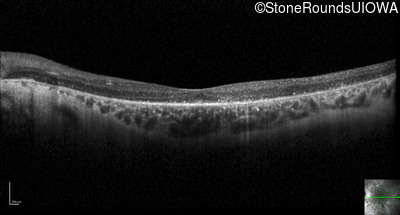

Optical Coherence Tomography - Right - 20/60 +1 sc

Exemplar / OCT Stack

OCT Stack